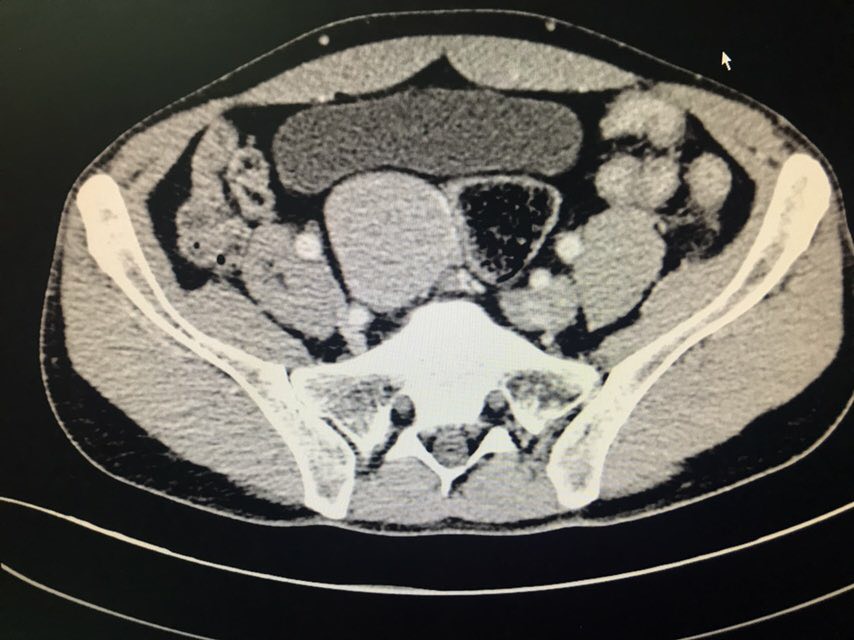

患者男性,43岁。主诉:发现盆腔占位1+月。现病史:患者1+月前于当地医院体检发现盆腔包块,于2018-08-28我院行泌尿系超声示:右侧髂窝实性占位伴钙化;2018-08-31我院行CT下腹部盆腔增强扫描示:下腹部及盆腔内多个软组织结节肿块影,肝右后叶上段囊肿;2018-09-07我院行病理检查示:盆腔肿瘤,倾向神经内分泌肿瘤,需行免疫组化染色检查;2018-09-07我院行膀胱超声示:超声引导下膀胱右侧盆腔内实性团块CNB。现患者为求手术治疗,于我院门诊就诊,以“盆腔肿瘤”收入我科。既往史无特殊。

查体:双侧腰部外形对称,皮肤无红肿,双肾区无叩痛,双肾下极未扪及,双输尿管行程区无压痛,膀胱区无隆起及压痛。双侧腹股沟区未扪及异常,无压痛;阴囊及尿道口未查。辅助检查:泌尿系超声(2018-08-28本院):右侧髂窝实性占位伴钙化;CT下腹部盆腔增强扫描(2018-08-31本院):下腹部及盆腔内多个软组织结节肿块影,肝右后叶上段囊肿;病理检查(2018-09-07本院):盆腔肿瘤,倾向神经内分泌肿瘤,需行免疫组化染色检查;膀胱超声(2018-09-07本院):超声引导下膀胱右侧盆腔内实性团块CNB。

患者膀胱右后方实性占位,穿刺活检倾向神经内分泌肿瘤,有手术指征。术中盆腔占位与周围重要组织器官粘连紧密,完整游离后整个创面较大,手术顺利,术后给予曲克芦丁脑蛋白水解物注射液2ml治疗。等待最终病理结果回报后制定下一步放化疗方案。